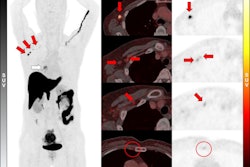

In a head-to-head comparison, F-18 fluroestradiol (FES)-PET/CT was better than standard FDG-PET/CT for the initial staging of estrogen receptor (ER)-positive breast cancer patients, according to a study published on December 18 in the European Journal of Hybrid Imaging.

In a retrospective analysis, a team in Bangkok, Thailand, found that F-18 FES PET scans detected more metastatic disease in patients than F-18 FDG-PET, with the authors ultimately suggesting the use of both radiotracers for the most accurate staging.

“F-18 FES-PET/CT could detect true metastatic lesions better than F-18 FDG-PET/CT,” noted first author Peerapon Kiatkittikul, MD, of the Chulabhorn Royal Academy’s National Cyclotron and PET Centre.

F-18 FDG is the most widely used PET radiotracer for evaluating various cancers, including breast cancer, the researchers noted. Conversely, F-18 FES-PET (Cerianna, GE HealthCare) was approved in the U.S. in 2020 for clinical use in patients with ER-positive cases as an adjunct to biopsy. Researchers are conducting ongoing work to define the clinical scenarios where the tracer may be most helpful, the authors noted.

To that end, in this study, the group compared the diagnostic performance of F-18 FDG and F-18 FES-PET/CT in the initial staging of ER-positive breast cancer. The group culled imaging from 28 breast cancer patients who underwent both scans for initial staging within two weeks at Chulabhorn Hospital in Bangkok between September 2020 and October 2022. Inclusion criteria were patients age 18 and older with pathologically confirmed cases.

According to the findings, the overall diagnostic performance of F-18 FES netted higher sensitivity, specificity, positive predictive value, negative predictive value, and accuracy, the researchers wrote.

“Diagnostic performance of strong ER expression was better in F-18 FES but worse for F-18 FDG,” the group wrote.

In addition, however, a subgroup analysis revealed that F-18 FDG-PET had significantly higher radiotracer uptake in ER-positive luminal B subtype breast cancer, which could indicate higher rates of cancer cell proliferation and potentially more aggressive tumors in these case, the authors noted.

“Hence, we propose that the combination of F-18 FDG and F-18 FES-PET/CT could overcome the limitation of each radiotracer while improving the accuracy for initial staging,” the group concluded.